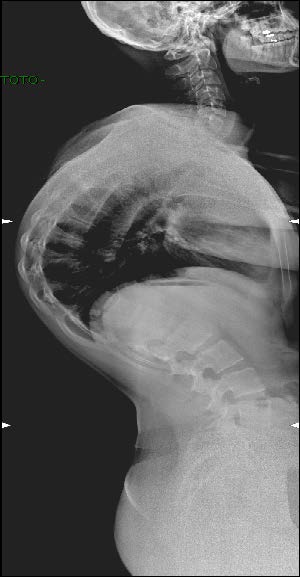

Quadro Clinico

- Il Dorso curvo

- Sede Toracica (apice tra T7 e T9) o Toracolombare (apice tra T10 e T12)

- IperLordosi lombare e cervicale di compenso

Cifosi dorsale rigida e dolorosa nell’adolescente

- Iperlordosi lombare non strutturata

- Antiversione della pelvi

- incurvamento delle spalle

La cifosi da Scheuermann è una tipica cifosi o dorso curvo dell’adolescenza da distinguere dalla cifosi posturale per la sua peculiare rigidità con dolore. Tre o piu’ corpi vertebrali adiacenti sono cuneizzati. Tipiche alterazioni delle limitanti somatiche. Alla deformità si associa una rachialgia dorsale (dorsalgia meccanica), che costituisce spesso il sintomo che porta alla consultazione.